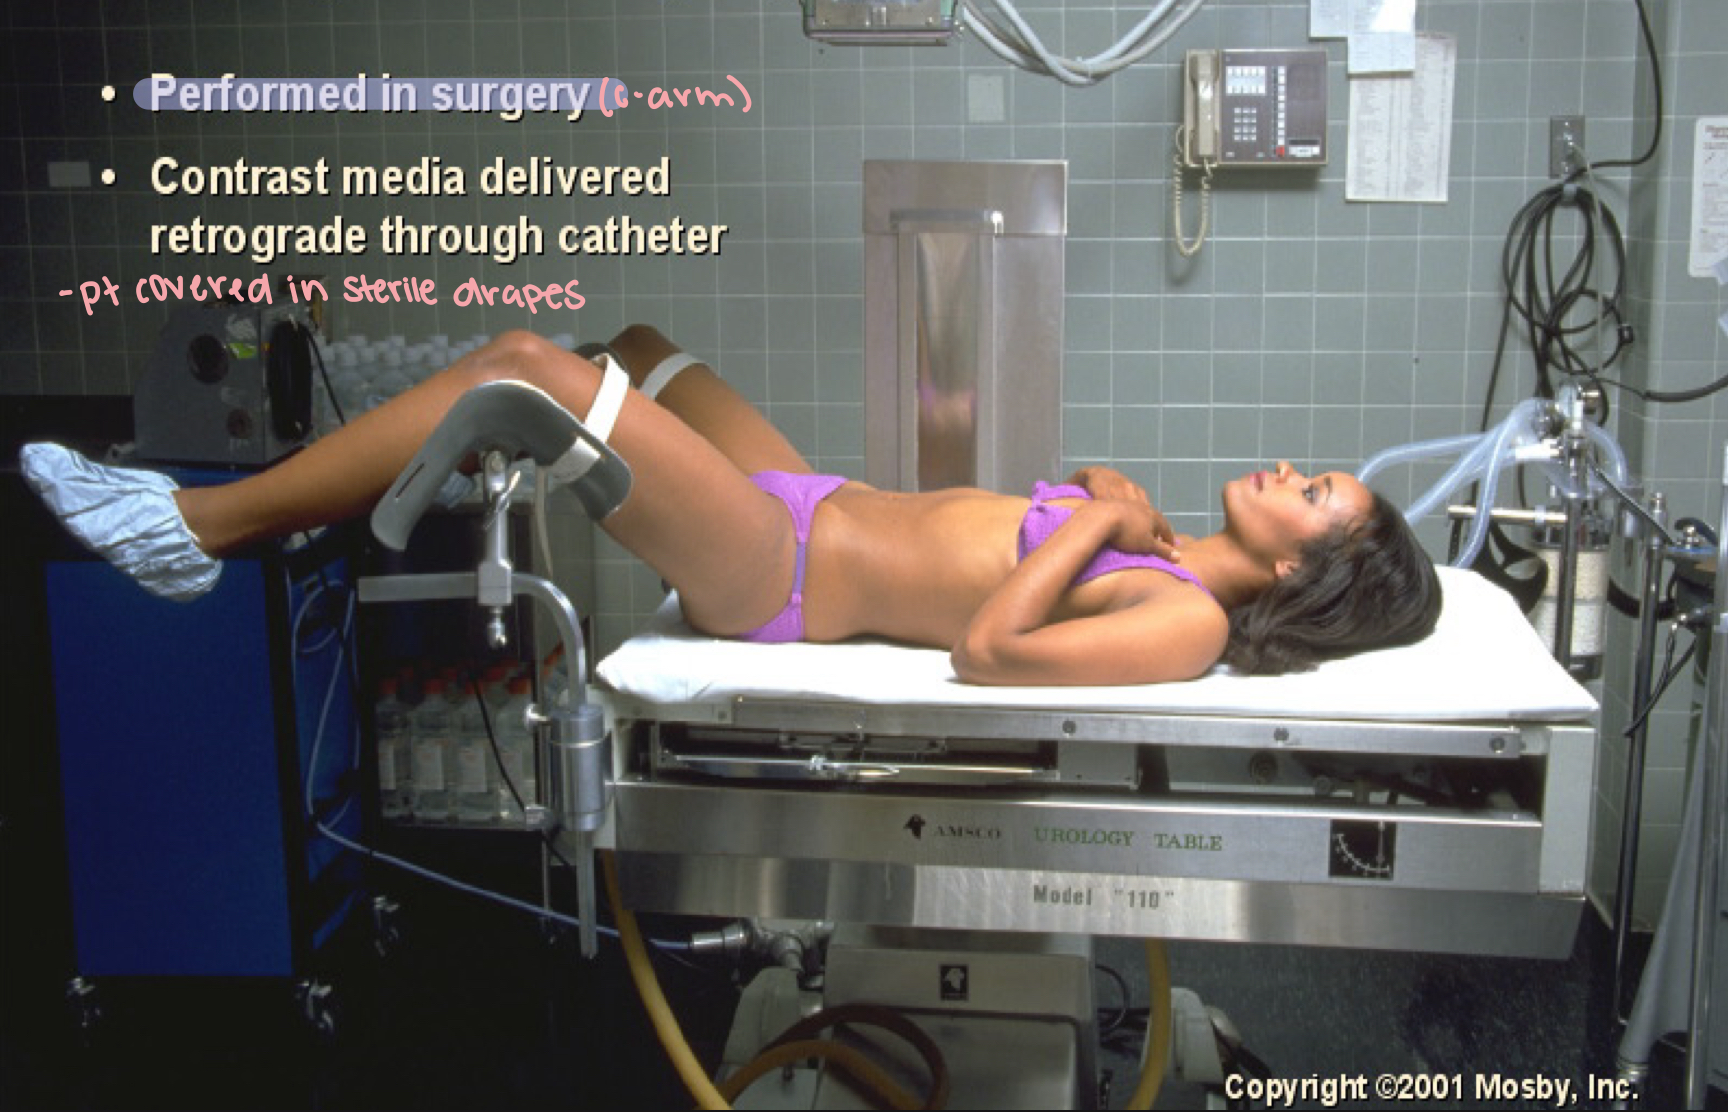

What position is this?

Retrograde urography